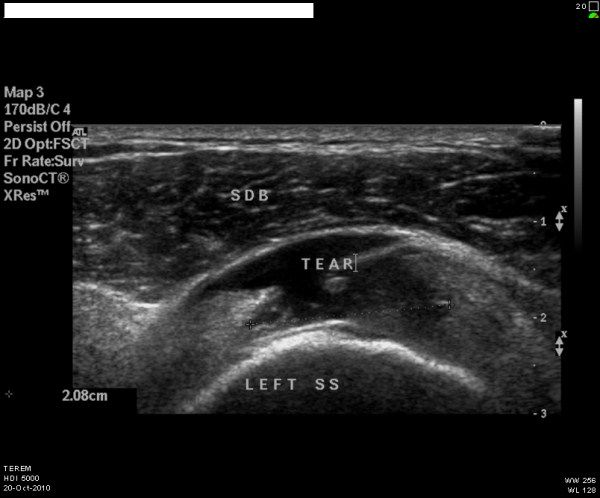

L’échographie est une technique d’imagerie médicale qui utilise les ultrasons pour étudier différentes parties du corps, notamment les muscles, tendons, ligaments, nerfs, autres tissus mous, la surface des os et des articulations. Elle permet de diagnostiquer des conditions telles que les entorses, les déchirures, les tendinopathies, les calcifications, les compressions de nerf, les inflammations articulaires et bien d’autres troubles du système neuro-musculo-squelettique.

La principale limitation de l’échographie est l’absorption des ultrasons par les os et sa réfraction totale par l’air. Ainsi, en cas de suspicion de lésion intra-osseuse ou intra-articulaire, une autre forme d’imagerie comme l’IRM ou le CT-Scan peut être prescrite. Dans certains cas, des radiographies peuvent également être nécessaires pour compléter l’examen échographique.